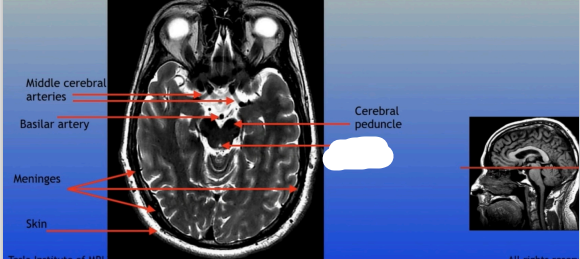

Middle Cerebral Arteries

Basilar Artery

Meninges

Skin

Cerebral Peduncle